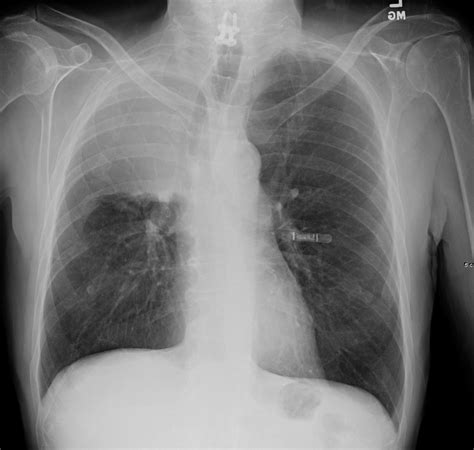

Diagnosing Atelectasis Lung Cancer involves a combination of medical history, physical examination, and diagnostic tests. The diagnostic process typically includes:

• Chest X-ray: An initial imaging test to detect any abnormalities in the lungs.

• CT Scan: A more detailed imaging test that provides a clearer picture of the lung tissue and any potential tumors.